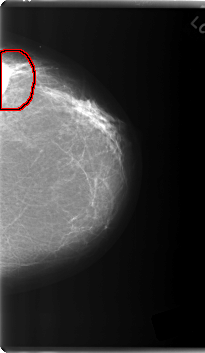

C_0219_1.LEFT_MLO

LEFT_MLO LINES 6000 PIXELS_PER_LINE 3680 BITS_PER_PIXEL 12 RESOLUTION 50 OVERLAY

FILE: C_0219_1.LEFT_MLO.OVERLAY

TOTAL_ABNORMALITIES 1

ABNORMALITY 1

LESION_TYPE MASS SHAPE LOBULATED MARGINS CIRCUMSCRIBED

ASSESSMENT 5

SUBTLETY 5

PATHOLOGY MALIGNANT

TOTAL_OUTLINES 1

BOUNDARY